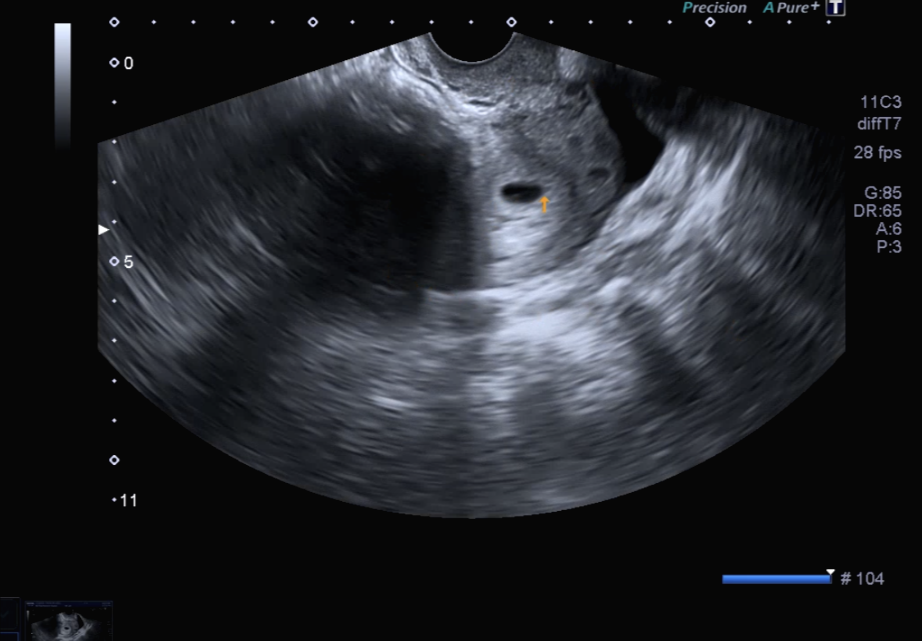

아직은 네가 너무 작은 존재라 배 초음파로는 너를 볼 수 없다고 하더라, 질 초음파를 통해 아기집을 처음 확인했단다.

의사 선생님께서 지금 아기집은 10mm 정도가 된다고 알려주셨어. (10mm 맞나?)

아직 엄마는 아기집밖에 보지 못했지만 2주 뒤에 오면 아가를 볼 수 있다고 알려주셨었어.